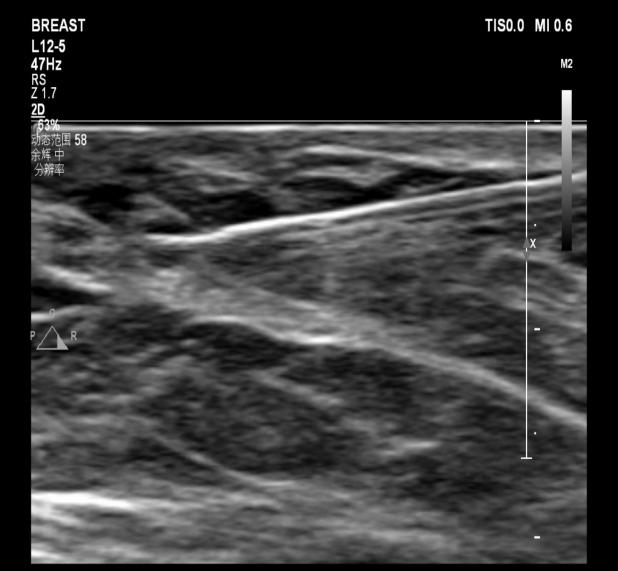

67岁的石女士(化名)在体检时发现了 “乳腺结节”,随后前来我院门诊就诊。经过超声检查,显示其左侧乳腺乳晕后方存在一枚实性结节,大小约为6×4mm,同时伴有局部乳导管的扩张情况。而超声造影结果表明,该结节呈现出快速高增强,且增强范围与二维图像保持一致,其BI-RADS分类为4a类,提示有导管内乳头状瘤的可能性。

在手术过程中快速捕获微小乳腺结节并实施完整切除是一项挑战。为了能够实现精准微创诊疗,我院普外科和超声科的医生们经过仔细讨论后,决定在术前对石女士的这枚乳腺小结节实施超声引导下定位针置入术。

超声引导下定位针置入术

超声引导下定位针置入术是对不可触及的可疑恶性的微小乳腺结节,利用一根纤细、尖端带钩的穿刺针,在超声实时动态监测下,经皮穿入结节内,释放穿刺针内的倒钩,钩住病灶,轻退穿刺针,将倒钩留于结节内,再将连于倒钩的导丝固定于体表。外科手术时,医生顺着导丝便能轻松捕获结节。

目前,我院超声科已常规开展此项技术。最终,石女士的结节通过手术被快速完整切除,病理诊断为导管内乳头状瘤。